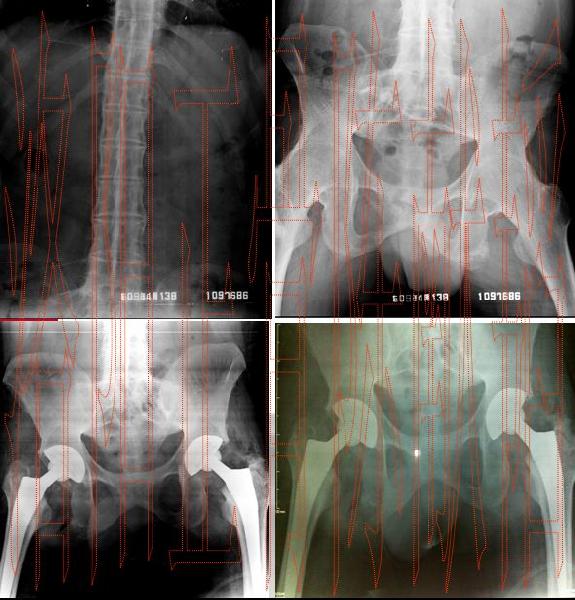

生活中得了强直性脊柱炎,很多患者都提心吊胆的, 生怕给自己的生命造成威胁。强直性脊柱炎有哪些危害?答案是肯定的。强直性脊柱炎,是关节病的一种,传统疗法统称为"痹症"。本病是由于椎间盘病变从而导 致上下椎体骨赘增生,压迫神经根、脊髓或影响椎动脉供血,引起脊椎炎症的疾病。所以患者在发现此病的时候,一定要及早的治疗。

从生活 方面看,强直性脊柱炎就是人体的脊柱弯曲,从外形上看就是严重的驼背,像大虾一样弯曲,脊柱关节完全融合在一起,不能弯曲活动。强直性脊柱炎不单纯是脊柱 的弯曲,全身各个大关节都可弯曲不能活动,如髋关节强直、膝关节强直、踝关节强直、肩关节强直等,强直性脊柱炎是能够造成人体严重残疾的一种疾病。